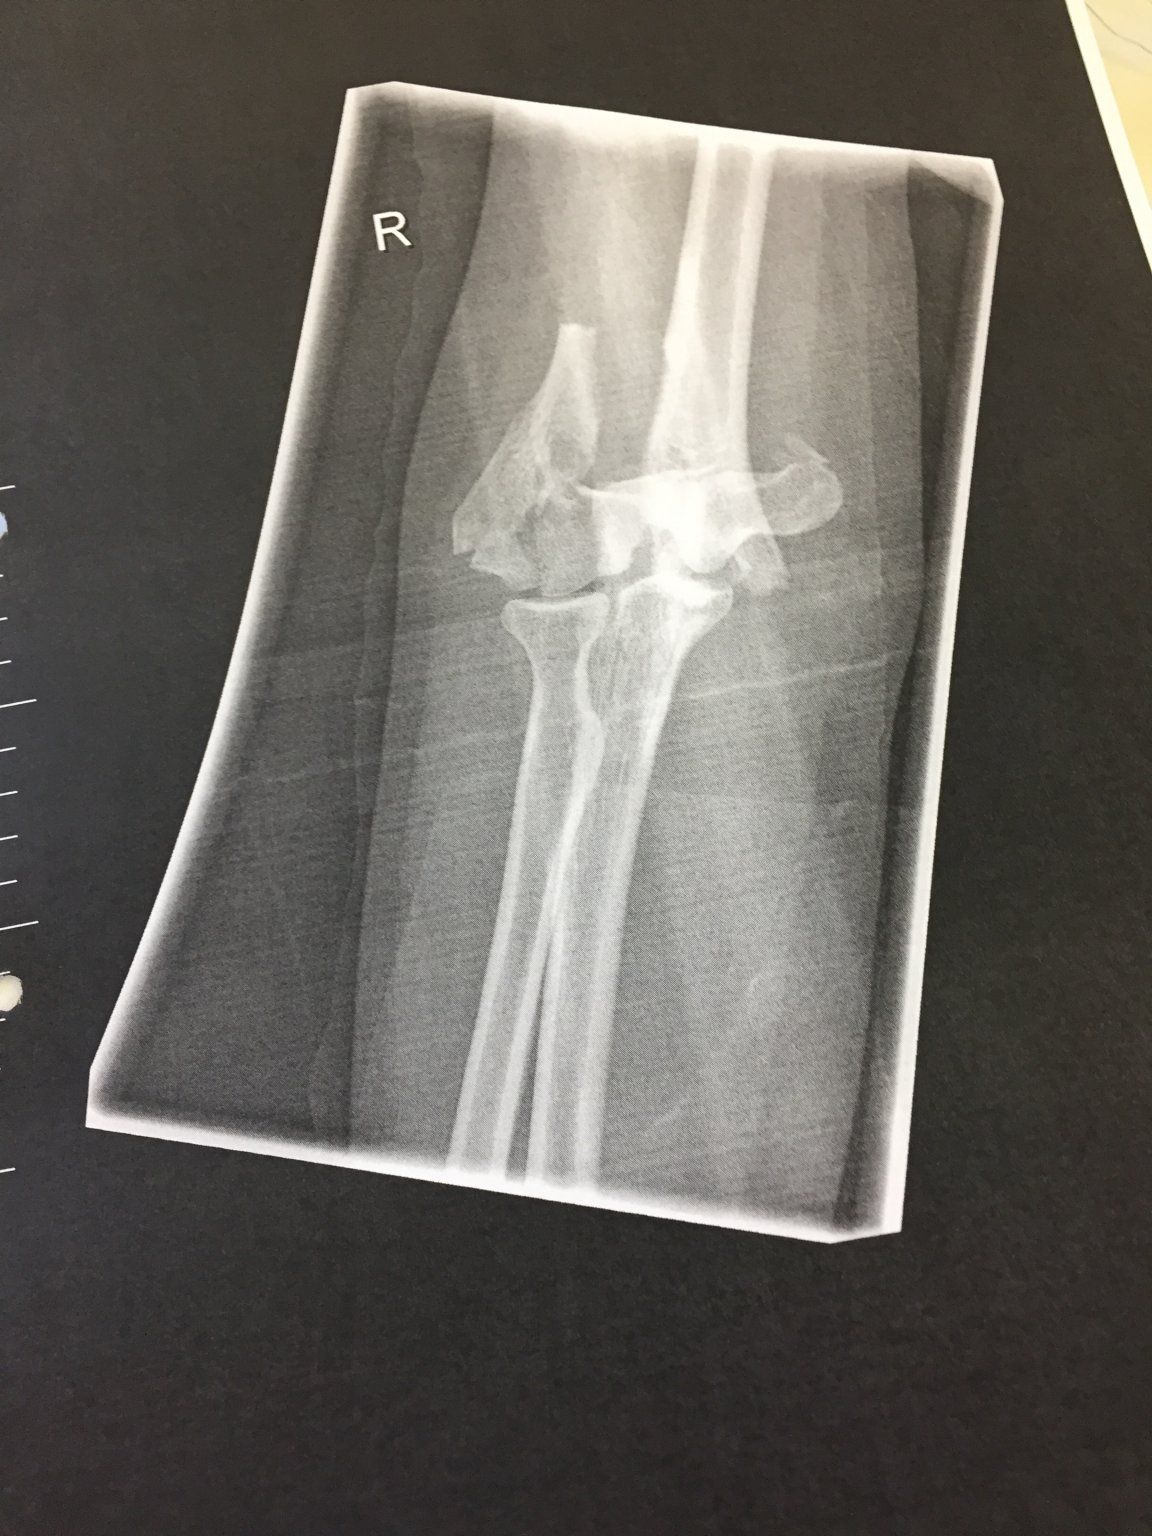

aber seit ich mich damit nicht mehr stresse, habe ich das Gefühl, dass es schneller voran geht. Trinken und und so weiter kann ich auch erst seit circa 1 Woche wieder... also das kommt alles mit der Zeit. Mit Gewalt würde ich da allerdings nicht rangehen, das solltest du dem Physio überlassen. Würde dazu auch deinen Chirurg und den Physiotherapeuten befragen. Die sollten am besten wissen, was für Übungen du zu Hause machen kannst. Darfst du den Arm denn schon wieder belasten? Volle Belastung (also Liegestütze und abstützen) sind bei mir erst nach 3 Monaten erlaubt. Und Sport darf ich auch erst nach 8 Wochen wieder machen. Würde auch gerne wieder Joggen etc., aber mir wurde gesagt, dass ich aufgrund der Erschütterung darauf verzichten soll. Allerdings haben wir auch nicht gleichen Bruch, bei mir war das Gelenk gebrochen, bei dir geht es bestimmt schneller.